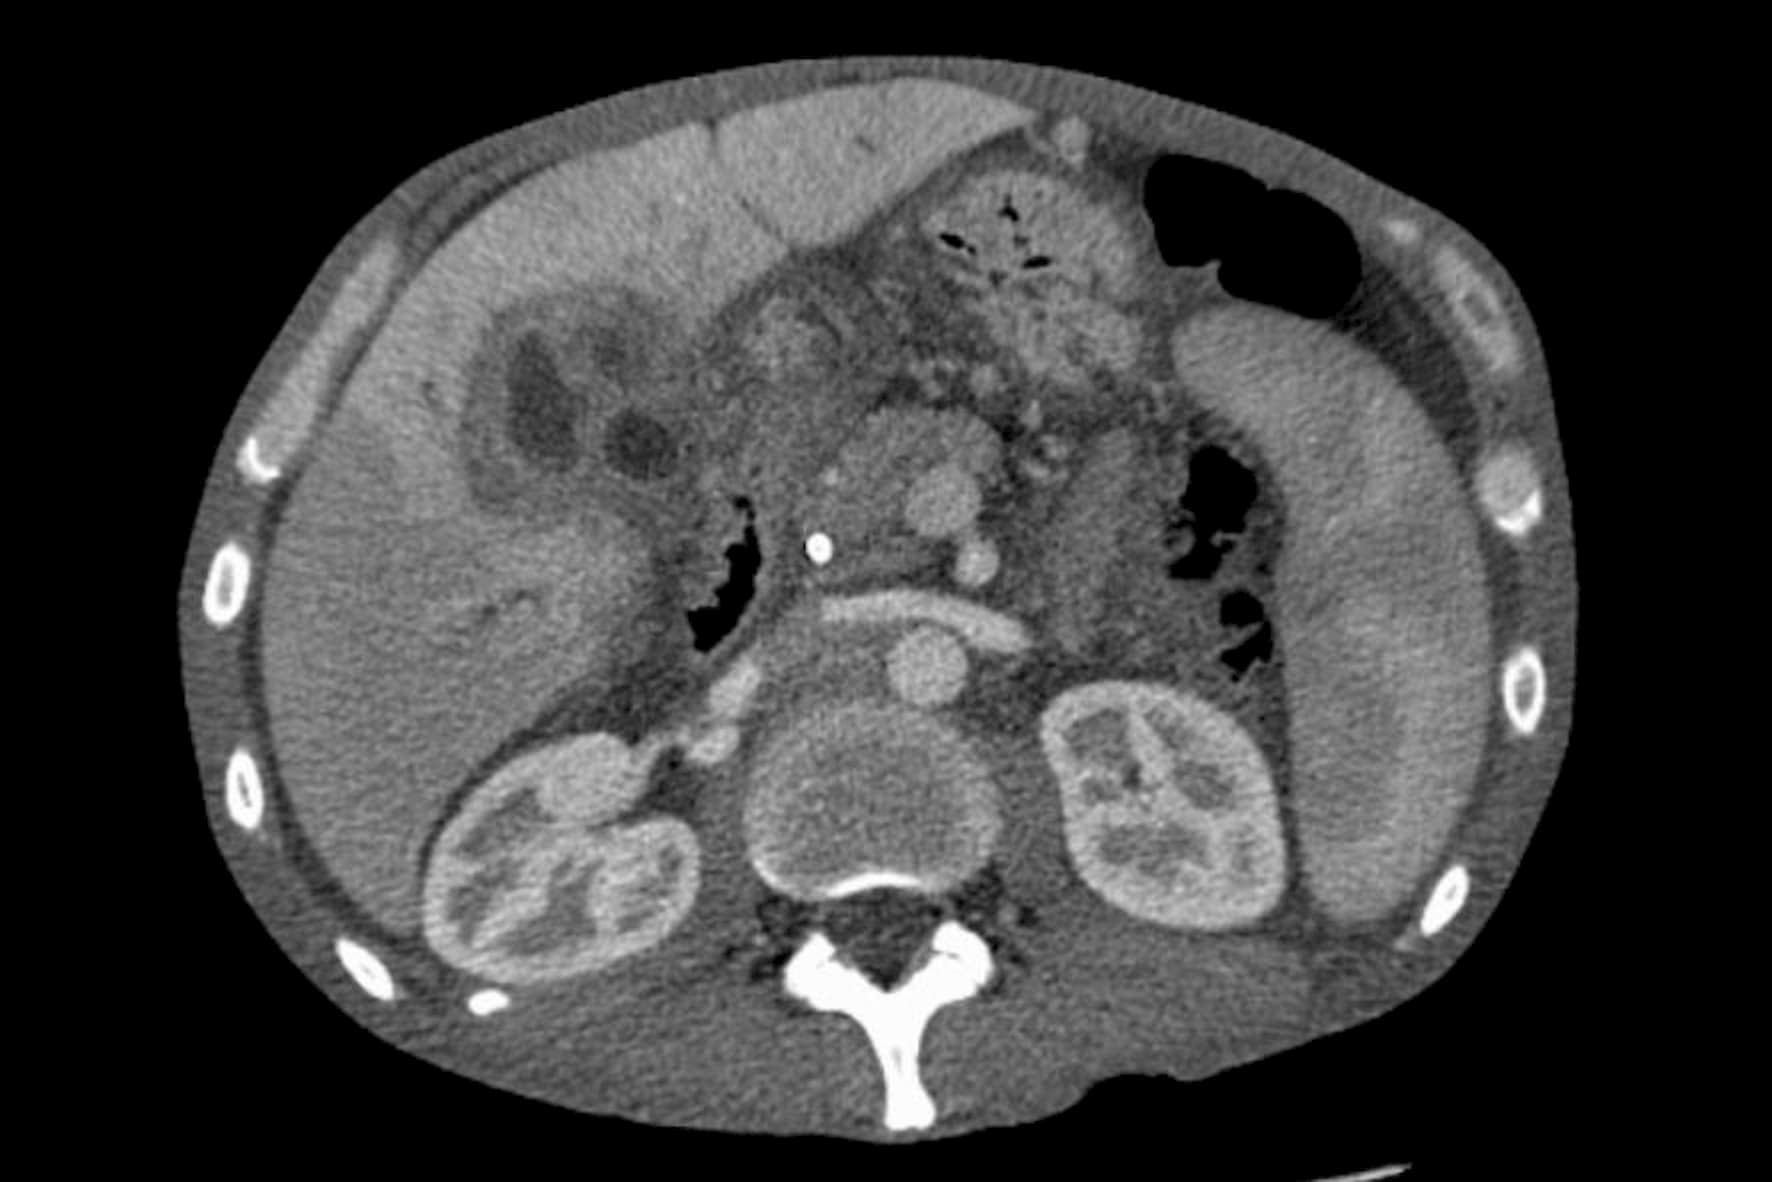

간암의 검사와 진단은 우선 의사의 문진과 진찰을 통해서 실시됩니다. 간암이 의심되는 경우 복부 초음파, CT, MRI등의 영상 진단을 중심으로 혈액 검사를 보조적으로 실시합니다.

복부 초음파 검사를 통해서 암의 크기와 수, 혈관과의 위치 관계, 확대된 정도, 간 모양이나 상태, 복수의 유무를 확인합니다. CT, MRI는 암의 유형, 전이 여부와 침윤 상황 등을 확인하며 더 확실하게 장기의 상태나 병변을 확인하기 위해 조영제를 이용하는 경우도 있습니다. 혈액 검사에서는 ALT(GPT), AST(GOT), γ-GTP 등의 값을 확인해서 간의 기능을 조사합니다.